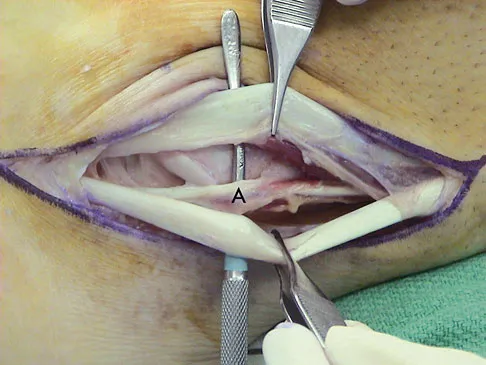

Figures 50a and 50b show the standing clinical photographs of a 12-year-old boy who has had increasing pain in the left foot for the past 9 months. He reports that the pain is activity related, aching in nature, and localized to the medial aspect of the midfoot and hindfoot. History reveals that he sustained a puncture wound located superior and posterior to the medial malleolus from a plate glass window 18 months ago. Examination reveals no restriction of ankle or subtalar motion, normal neurovascular status, no masses, and a well-healed 1.5-cm laceration posterior to the superior aspect of the medial malleolus. Inversion strength of the foot is decreased to grade 3/5. Radiographs of the foot show no bony abnormalities. Treatment should consist of

Explanation